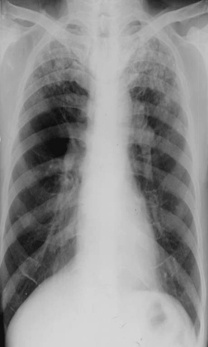

斑片狀陰影位于雙肺尖,根據公式診斷浸潤性肺結核